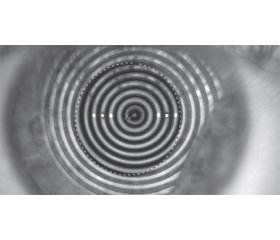

Актуальність. На сьогодні актуальною проблемою є пандемія коронавірусної хвороби 2019 (COVID-19) в усьому світі. Вжито заходів безпеки, зокрема використання масок, дистанційне навчання. Однак офтальмологи, як і населення в цілому, повинні знати, що маска для обличчя разом із тривалим використанням цифрових пристроїв призводить до збільшення кількості повідомлень про сухість очей у великої кількості пацієнтів. Мета дослідження: вивчити частоту виникнення хвороби сухого ока у студентів з міопією. Матеріали та методи. У дослідженні взяли участь 96 студентів медичного університету, які спостерігались у офтальмолога з діагнозом «міопія», обраних методом випадкової вибірки. Всім пацієнтам, крім стандартного офтальмологічного обстеження, проводилась оцінка стабільності прерогової слізної плівки (CП) за допомогою кератотопографії рогівок, та проба Норна (час розриву слізної плівки (ЧРСП)). Також використовувався стандартний опитувальник, призначений для оцінки вираженості симптомів хвороби сухого ока, «Індекс ураження очної поверхні» (Ocular Surface Disease Index). Результати. Під час проведення кератотопографії в 47 пацієнтів ЧРСП не був знижений. У середньому за часом стабільність концентричних кілець зберігалась тривалий час, 20,2 ± 3 с. Але у 49 пацієнтів спостерігались ознаки нестабільності СП за часом порівняно з 47 пацієнтами без порушення ЧРСП. У 47 пацієнтів без порушень при дослідженні на корнеотопографі даний показник при пробі Норна варіював від 25 до 18 с, тобто також не виходив за рамки вікової норми (у середньому 21,5 ± 3,5 с). У 3 пацієнтів з мінімальним показником ЧРСП за кератотопографією його значення за пробою Норна становило 9 с. У 36 пацієнтів з укороченням ЧРСП, відповідно до обох методів, відзначався слабкий ступінь сухого ока, у 10 — помірний, у 3 — виражений. Найбільш частими скаргами були: відчуття піску в очах, зоровий дискомфорт при роботі за комп’ютером і в вітряну погоду та при тривалому користуванні захисною маскою. Висновки. Серед студентів, які перебували на дистанційному навчанні, в 51,04 % випадків відзначається підтверджена об’єктивними методами хвороба сухого ока. Більш виражений ступінь сухого ока відзначається в користувачів контактних лінз, тому в обов’язковому порядку офтальмологам слід призначати їм зволожуючі краплі.

Background. Today, the urgent problem is coronavirus disease 2019 pandemic in the whole world. Safety measures such as the use of masks, distance learning have been implemented. However, ophthalmologists, as well as the general population, should know that a face mask together with prolonged use of digital devices leads to an increase in the number of dry eye cases in many patients. The purpose was to study the frequency of dry eye disease in students with myopia. Materials and methods. The study involved 96 medical students diagnosed with myopia taken by random sampling, who were examined by an ophthalmologist. Apart from the standard ophthalmologic examination, all patients underwent the evaluation of the stability of the precorneal tear film by means of corneal topography, and Norn test (tear break-up time (TBUT)). There was also used a standard questionnaire designed to assess the severity of dry eye disease symptoms (Ocular Surface Disease Index). Results. The corneal topography of the 47 patients did not demonstrate any reduction in TBUT. The average time of the concentric ring remained stable for 20.2 ± 3.0 seconds. But 49 individuals exhibited signs of tear film instability over time compared to 47 patients without TBUT impairment. In 47 people without impairments, corneal topography demonstrated that this indicator in Norn test varied from 25 to 18 seconds, i.e. was within the age norm (21.5 ± 3.5 seconds on average). In 3 patients with a minimum TBUT on keratotopography, its value during the Norn test was 9 seconds. In 36 patients with reduced TBUT according to both methods, there was a weak degree of dry eyes, in 10 — moderate, in 3 — severe. The most common complaints were a sandy, gritty sensation in the eyes, visual discomfort when working at a computer and in windy weather, and with prolonged use of a protective mask. Conclusions. Among students who were on distance learning, 51.04 % of individuals have objectively confirmed dry eye disease. People wearing contact lenses have a more pronounced degree of dry eye, so it is mandatory for ophthalmologists to prescribe lubricating eye drops.